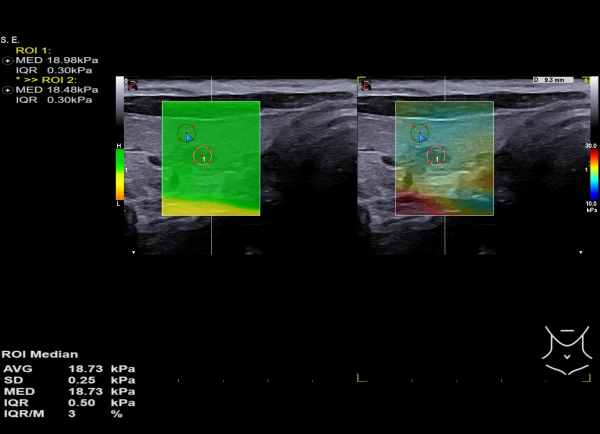

Qalqonsimon bez va sut bezlarida shubhali joylarni avtomatik konturlash;

Ko'krak massasini tahlil qilish. Qiziqarli sohada sut bezlari o'smalarini tasniflash bo'yicha avtomatik taklif;